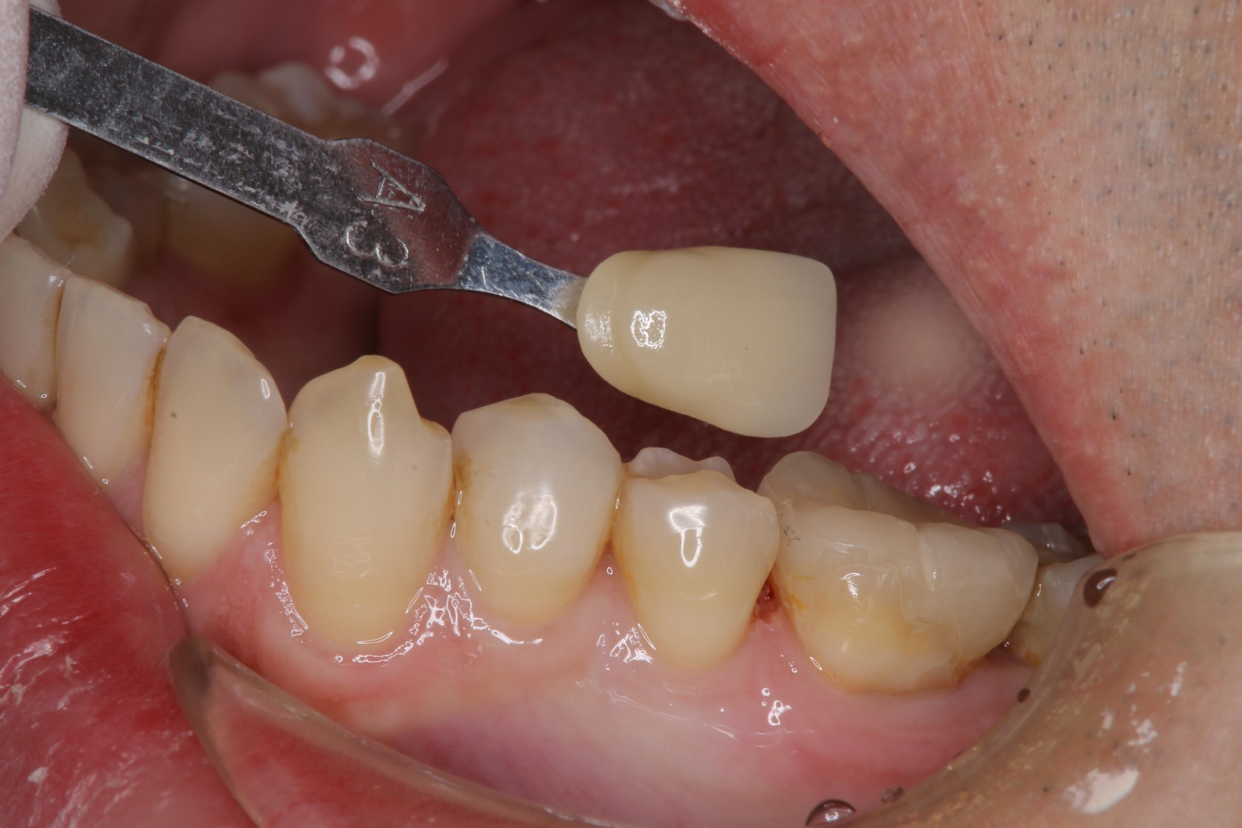

臨床照相比色